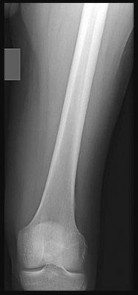

Question 5:

A 22-year-old collegiate football player sustains a twisting injury to his knee during a tackle. Radiographs reveal an avulsion fracture of the lateral aspect of the proximal tibia, just distal to the articular surface (a Segond fracture). Which ligamentous injury is most strongly associated with this pathognomonic finding?

Correct Answer: Anterior cruciate ligament (ACL) tear

Explanation:

A Segond fracture is an avulsion fracture of the anterolateral capsule and the anterolateral ligament (ALL) complex from the lateral tibial plateau. It is considered pathognomonic for an anterior cruciate ligament (ACL) tear. It typically occurs via an internal rotation and varus stress mechanism.